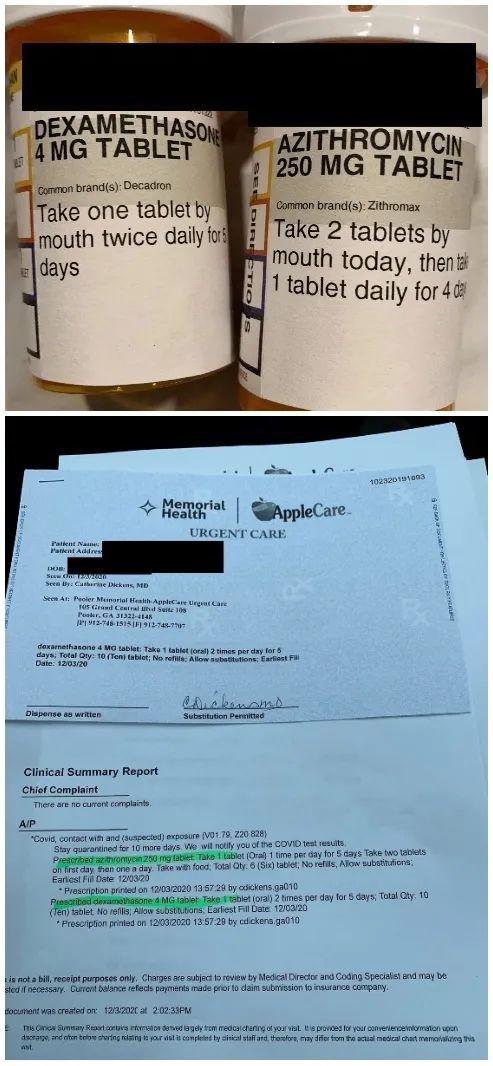

医生给我开了4天的处方药,分别是消炎药和抗生素,而宝宝目前没有专门治疗新冠的药可吃,所以如果发烧的话,还是吃泰诺或感冒药。 我们每天都有吃维他命,包括维B、维C、维D3,我还做了鸡汤每天喝,而且一直有吃感冒药。Boss就继续喝苹果洋葱水,以及吃Gummy Bear补充维他命。